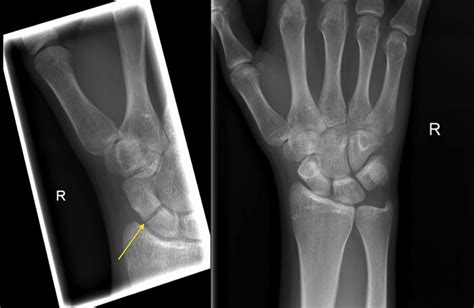

Diagnosing a Broken Scaphoid Bone

Diagnosing a broken scaphoid bone involves a combination of physical examination and imaging tests. A healthcare provider will typically:

• Order imaging tests, such as X-rays, to visualize the bone

However, X-rays may not always show a scaphoid fracture, especially in the early stages. In such cases, additional imaging tests may be required, including:

These tests can provide more detailed images of the bone and surrounding tissues, helping to confirm the diagnosis and assess the extent of the injury.